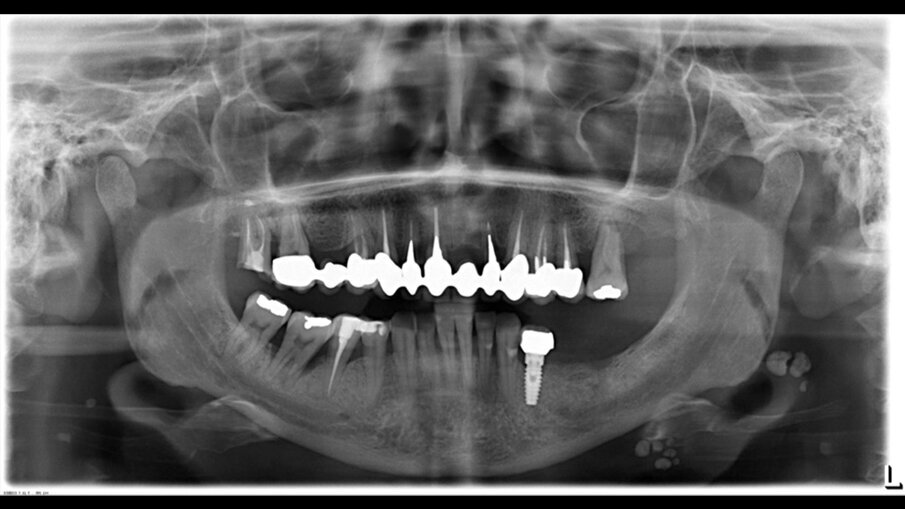

Sulle suture viene applicato l’olio di oliva evo ozonizzato attivato Perioral 3 (Gemavip), che unisce l’efficacia terapeutica dell’olio di oliva alle molecole attive dell’ozono. Grazie a questo processo il prodotto vanta proprietà batteriche, fungicide e antinfiammatorie che svolgono un’azione mirata sulla riparazione epiteliale. Il cetylpyridinium svolge un’azione antisettica e battericida, la clorfenesina è un antimicotico e un miorilassante. Il collagene a basso peso molecolare è facilmente assorbibile e lavora per la rigenerazione cellulare. L’acido ialuronico a basso e alto peso molecolare coadiuva la rigenerazione cellulare. Viene dato alla paziente un bite anteriore di svincolo per riposizionare la mandibola e dopo una settimana viene registrata la posizione delle arcate. Vengono posizionati i nuovi provvisori con le nuove registrazioni occlusali. Nel frattempo vengono inseriti 4 impianti in zona 35, 36, 46 (post estrattivo a carico ritardato con rigenerazione guidata GBR) e in zona 26 a carico ritardato, mentre era già presente un impianto in zona 34 che presentava un minus cervicale con estetica carente (Fig. 7).

Fig. 7 - Inserimento impianti e radiografie di controllo.